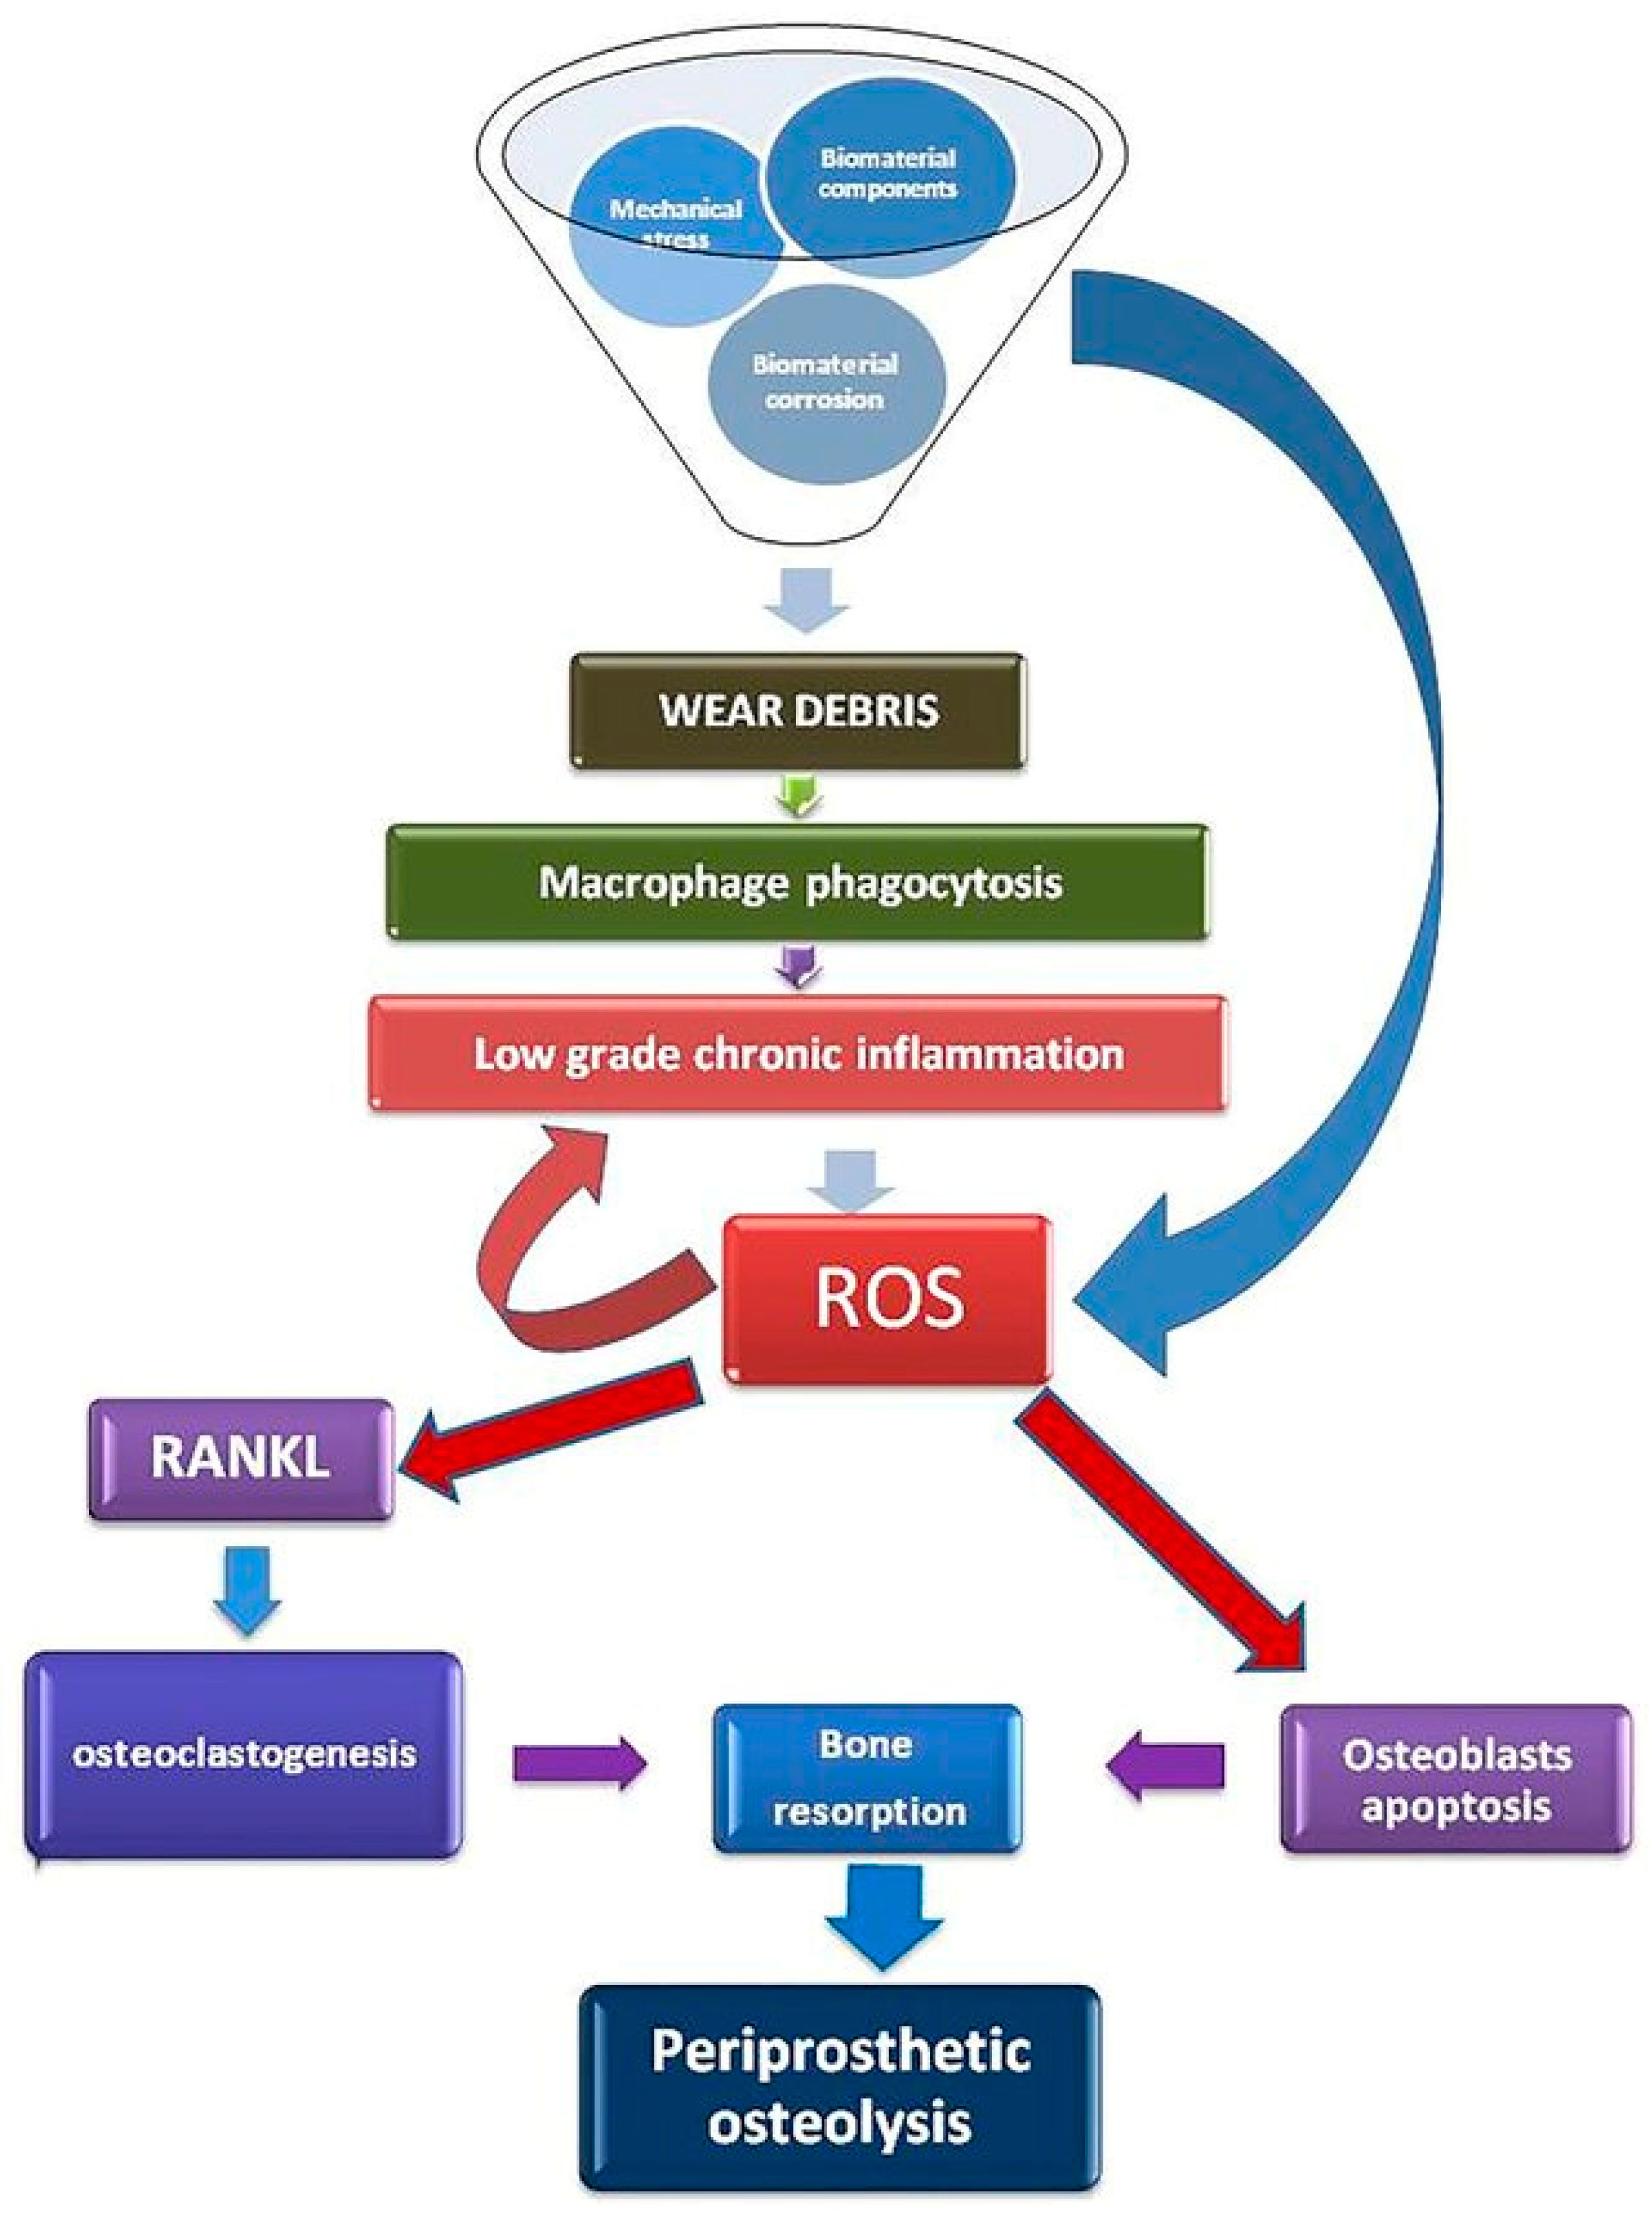

6. Liposomes Detect Oxidative Stress and Enhance the Bone-Healing Process

8. Liposomes to Observe the Degradability of Implants